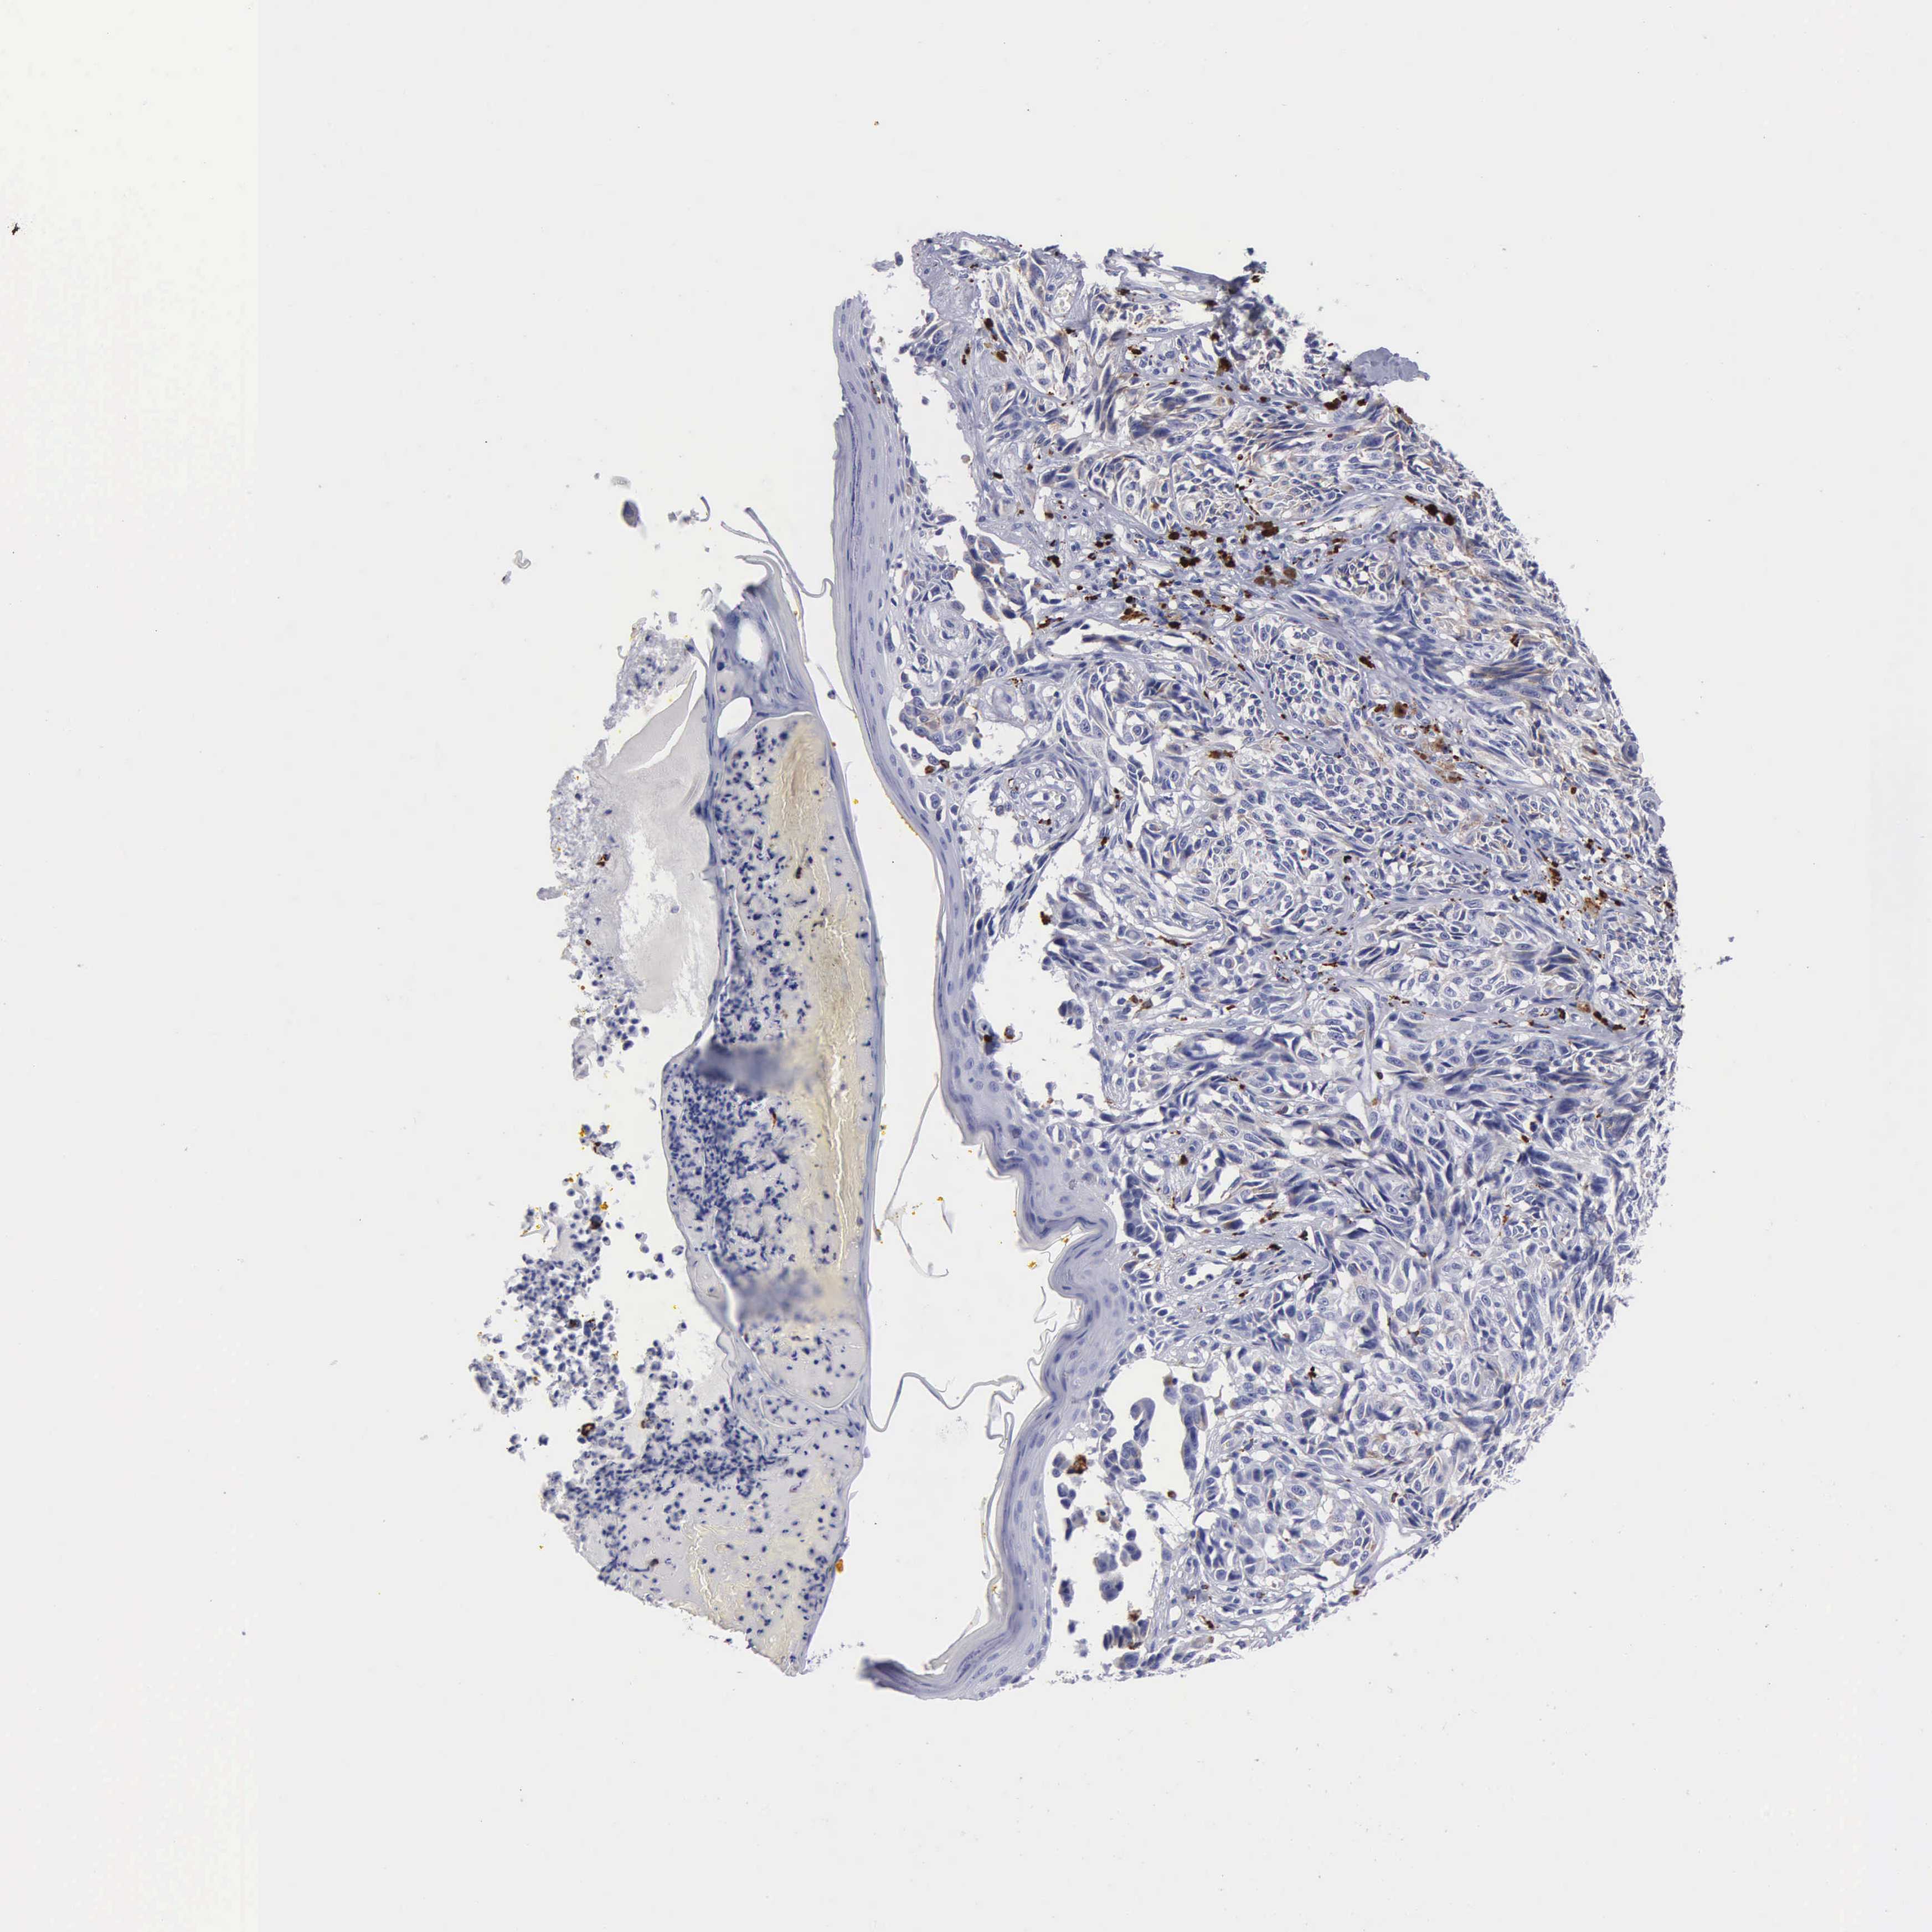

MELANOMA - Protein expressioni

A mouse-over function shows sample information and annotation data. Click on an image to view it in a full screen mode. Samples can be filtered based on level of antibody staining by selecting one or several of the following categories: high, medium, low and not detected. The assay and annotation is described here.

Note that samples used for immunohistochemistry by the Human Protein Atlas do not correspond to samples in the TCGA dataset.

Antibody stainingi

Antibody staining in the annotated cell types in the current human tissue is reported as not detected, low, medium, or high, based on conventional immunohistochemistry profiling in selected tissues. This score is based on the combination of the staining intensity and fraction of stained cells.

Each image is clickable and will lead to virtual microscopy that enables deeper exploration of all samples and also displays staining intensity scores, fraction scores and subcellular localization as well as patient and tissue information for each sample.

Antibody CAB000459

Staining

High

Medium

Low

Not detected

Intensity

Strong

Moderate

Weak

Negative

Quantity

>75%

75%-25%

<25%

None

Location

Nuclear

Cytoplasmic/membranous

Cytoplasmic/membranous,nuclear

Malignant melanoma, Metastatic site